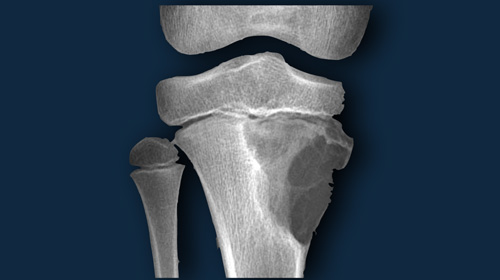

Cartilage tumors